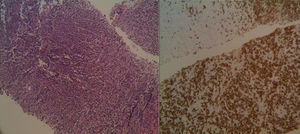

Se procede a la punción-biopsia de la zona hepática, con resultado AP de linfoma no Hodgkin de células B (CD20+) (figs. 4 y 5), que se mostró también en la biopsia realizada a posteriori a nivel renal.Posteriormente se procedió a iniciar terapia con rituximab.